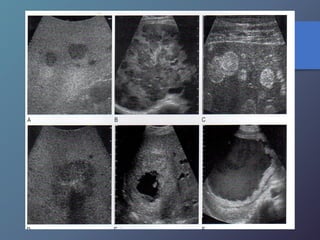

Mt Hiperecoicas

• Ecográficamente se presentan las lesiones

de tamaño variable con presencia de un

halo hipoecoico.

• Diferenciar lesiones malignas de benignas

por presencia de halo hipoecoico.

• Se describen como lesiones ecógenas,

hipoecoicas, en diana, calcificadas,

quísticas y difusas.

Clasificación de las Metástasis

MT ecogenas:

• origen digestivo o chc.

MT hipoecoicas:

• Son hipovasculares.

• Origen CA de mamas, pulmón, páncreas y esófago.

• Los linfomas hepáticos pueden manifestarse en masas

hipoecoicas, o difusas difíciles de diferenciar por ecografía

o TC.

MT en diana:

• Presentan una zona hipoecoica periférica, con centro

hiperecoico.

• Frecuente en carcinomas broncogenos.

MT calcificadas:

• Presentan una ecogenicidad acentuada y

marcada sombra Acústica

• Frecuentes en adenocarcinoma de colon,

gástricos, TU. Pancreaticos, leiomiosarcomas,

neuroblastomas, cistadenocarcinomas,

teratocarcinoma ováricos.

MT quísticas:

• Son poco frecuentes

• Son de paredes muy gruesas, presencia de

tabiques internos, ecos de nivel bajo.

• Pueden observarse en el cistadenocarcinoma

del ovario y del páncreas y en el carcinoma

mucinoso de colon.